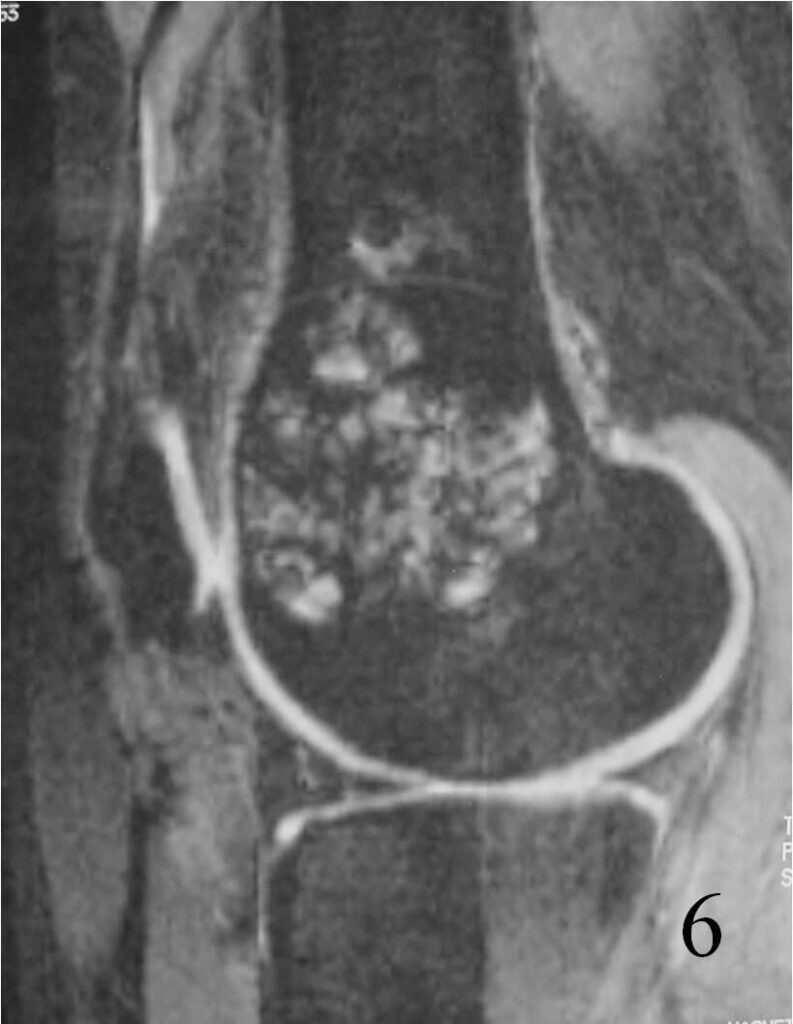

MRI

- They will be low to intermediate on T1-weighted images, and intermediate to high on T2-weighted images (Fig. 4, 5, 6)

Fig. 6 Sagittal T2 FS MRI shows high and low signal areas (heterogeneous)